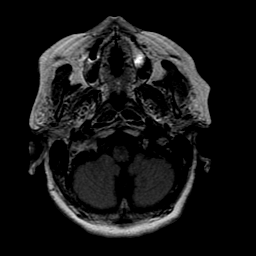

Stroke: proton density-weighted MR #1 -- Slice #2

[Home][Help][Clinical] Slice 2